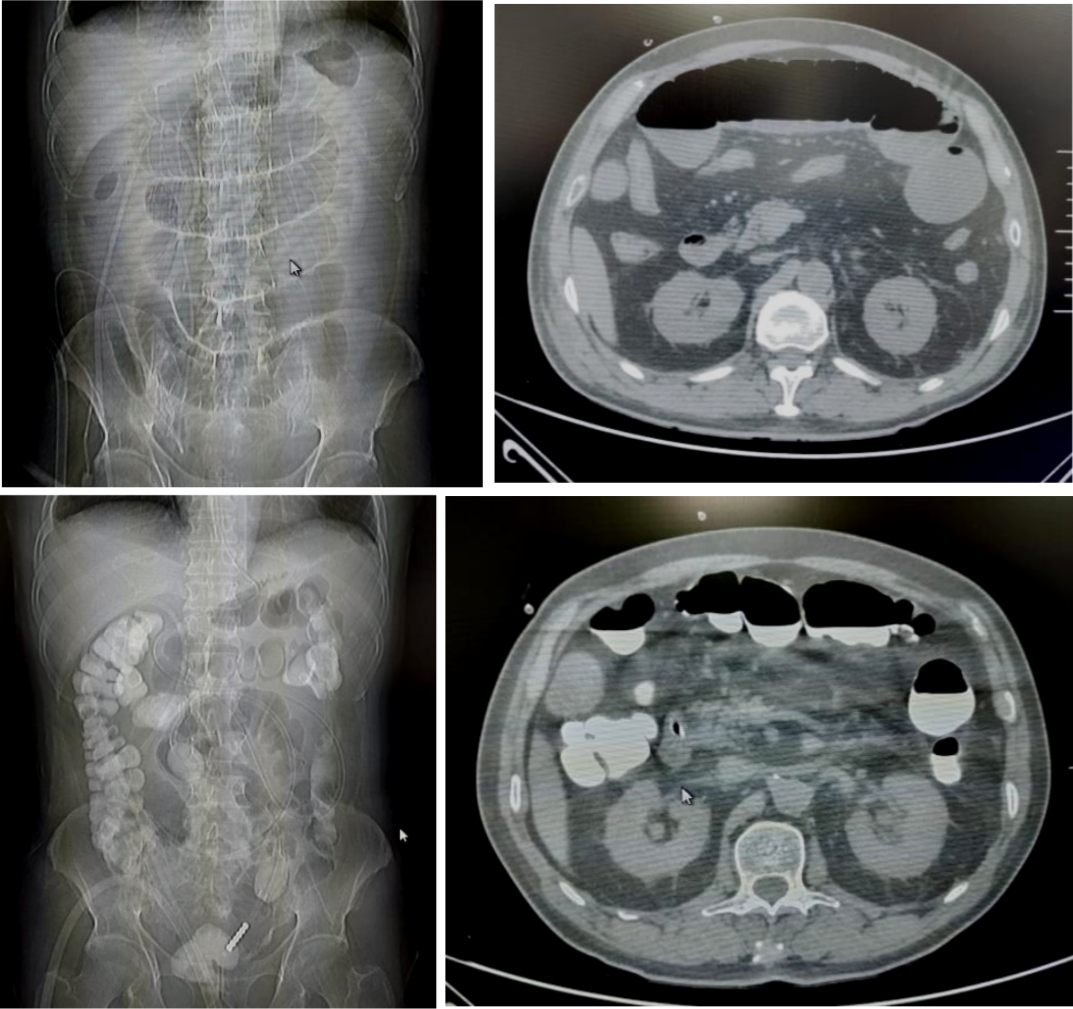

71岁的患者刘先生,因行膀胱癌根治术、回肠代膀胱术出现肠梗阻。后在我院放射介入室行DSA引导下经鼻肠梗阻导管置入术,术后当日患者腹胀较前明显缓解,术后第6天患者排气、排便,肠管恢复通畅,拔除肠梗阻导管。

18岁的患者叶女士,因行阑尾穿孔导致盆腔脓肿后出现肠梗阻。后在我院放射介入室行DSA引导下经鼻肠梗阻导管置入术,术后当日患者腹胀较前明显缓解,术后第3天患者排气、排便,肠管恢复通畅,拔除肠梗阻导管。